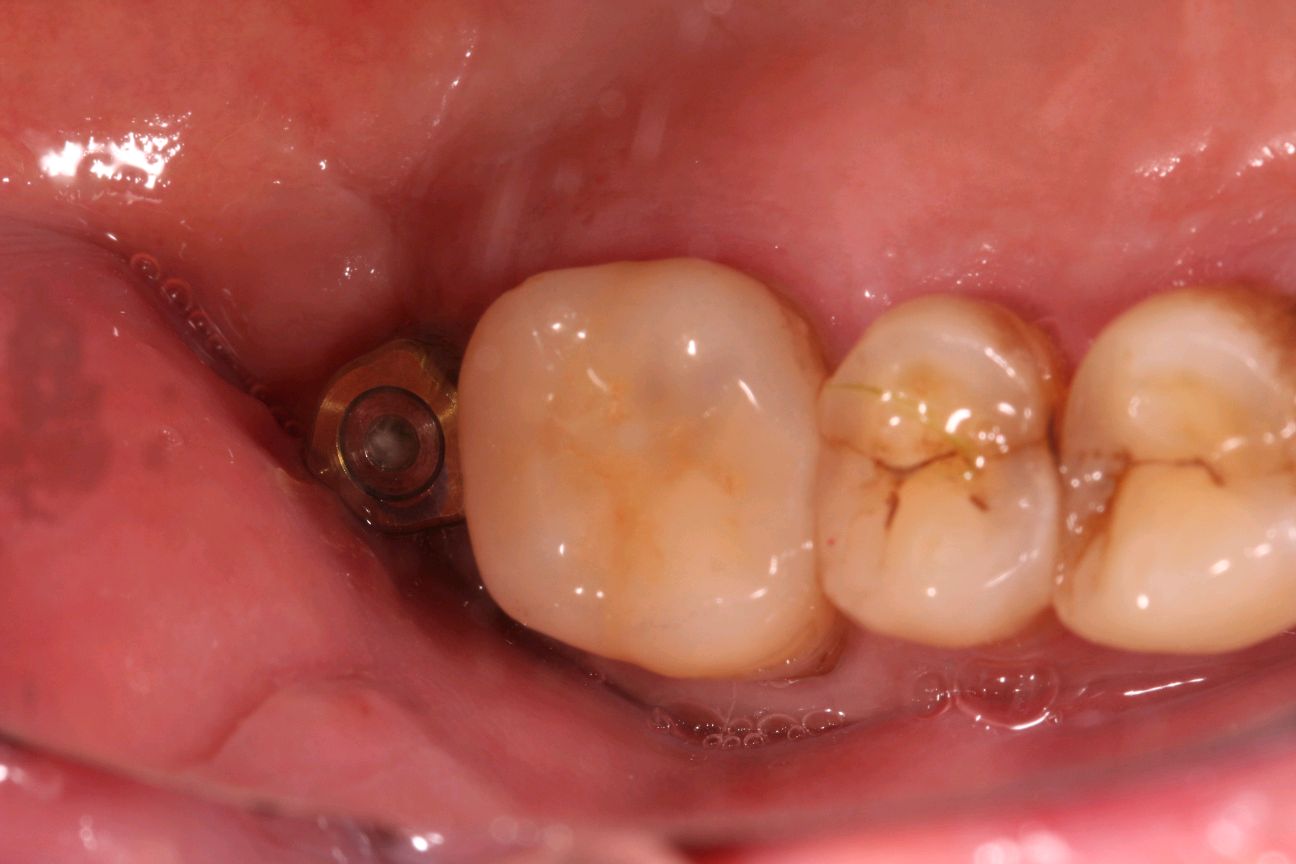

患者是成功人士,平时非常忙碌,忽略了口腔健康,直到有一天无法咀嚼食物后才想到要治疗牙齿,我们为他摄了CBCT,发现有重度牙周病,上合双侧7自然脱落,左上8,III度松动,并近中倾斜移位,对合牙严重伸长,还有其他牙齿疾患,需要综合治疗;经过牙周病治疗、上合窦骨增量、上合种植修复、拔牙、截冠、根管治疗、桩冠、高嵌体修复等!时间长达一年,终于恢复了正常牙列!可以享受食物的美好!